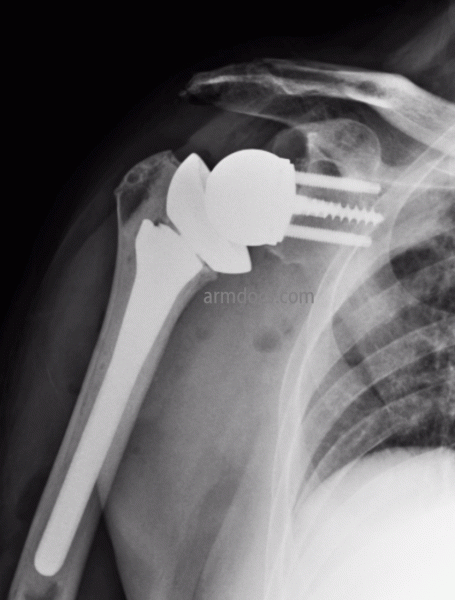

This protocol is applicable to patients treated surgically with a Reverse Total Shoulder Replacement.

Rotator Cuff Tear Arthropathy Reverse Shoulder Replacement